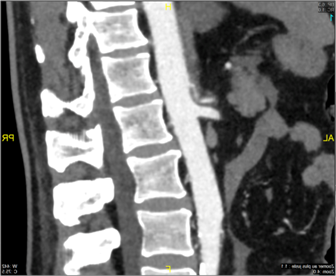

Il s’agit d’un homme de 59 ans, sans antécédents particuliers, victime d’un accident de la voie publique. Le bilan scanner à son arrivé ne montrait pas de franc saignement, ce qui justifiait en première intention une conduite conservatrice au vu des conditions hémodynamiques stables.

Fig. 1 Bilan scanner à l’entrée aux urgences J0